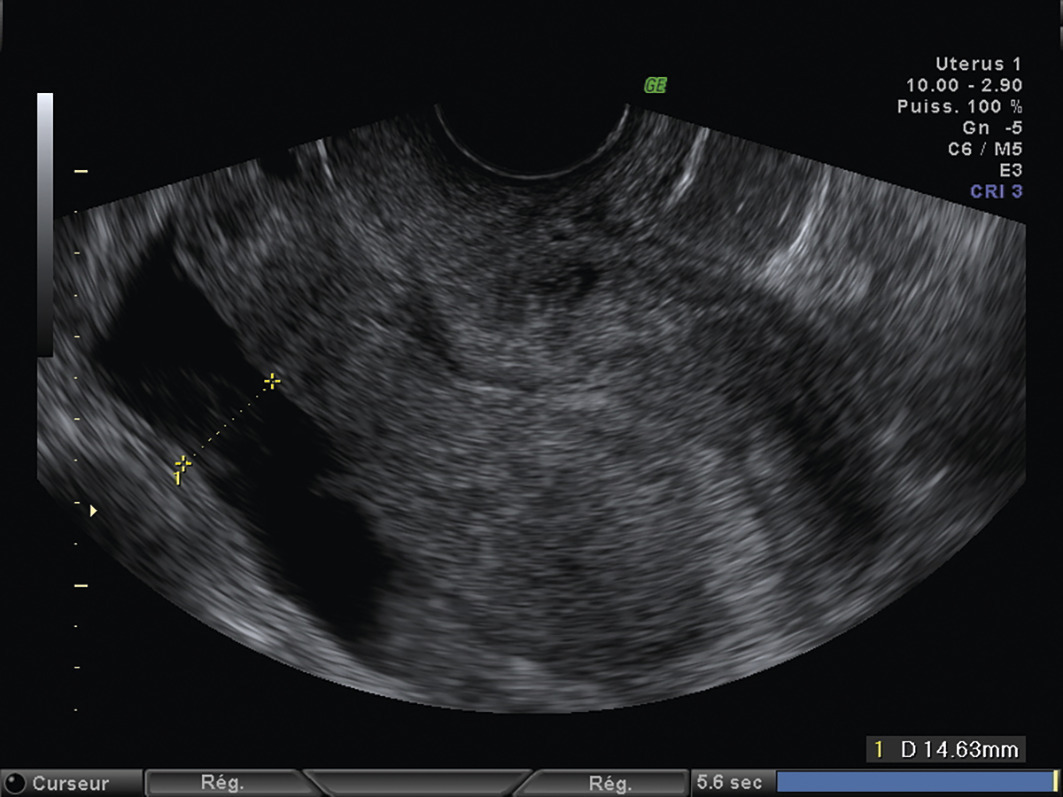

L’échographie, indispensable, doit examiner le pelvis mais aussi l’abdomen. Elle est donc réalisée par voie endovaginale, sus-pubienne et abdominale. On peut visualiser une masse latéro-utérine (fig. 1). Au sein de cet hématosalpinx, un sac gestationnel peut être visible, voire un embryon (fig. 2) ayant parfois une activité cardiaque positive. Le passage de la sonde à ce niveau est douloureux.

– vacuité utérine (fig. 3) et taux de hCG supérieur à 1 500 UI/L, fortement évocateurs. En cas de métrorragies, une lame d’hématométrie peut être visible en intra-utérin (« pseudo-sac gestationnel » : image hypo-échogène centrée dans la cavité, sans couronne trophoblastique) ;